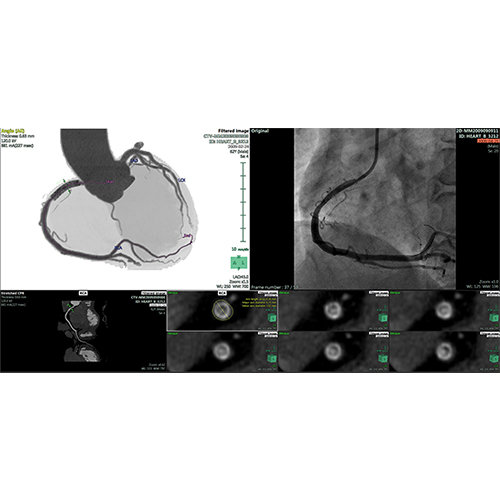

View X-Ray CT & MRI Scans Fast and Easily

Designed for surgeons, Pro Surgical 3D makes it easy to view patient scans quickly. Pro Surgical 3D facilitates the optimal 3D treatment and assessment workflows based on X-ray CT and MRI scans – and best of all, it’s FREE!

High-quality and fast 3D reconstruction and 3D rendering

Performs 3D reconstruction and volume rendering.

Multi-planar slicing.

Oblique slicing.

Side-by-side comparative assessment for pre- and post-operative scans.